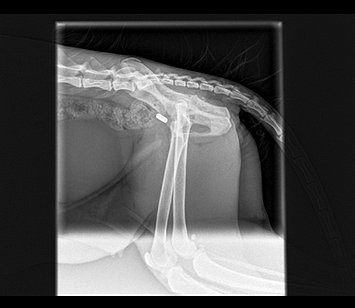

"Ernie" - Kitten with dislocated hip

"Ernie" - Kitten with dislocated hip from www.fairfieldvets.co.uk